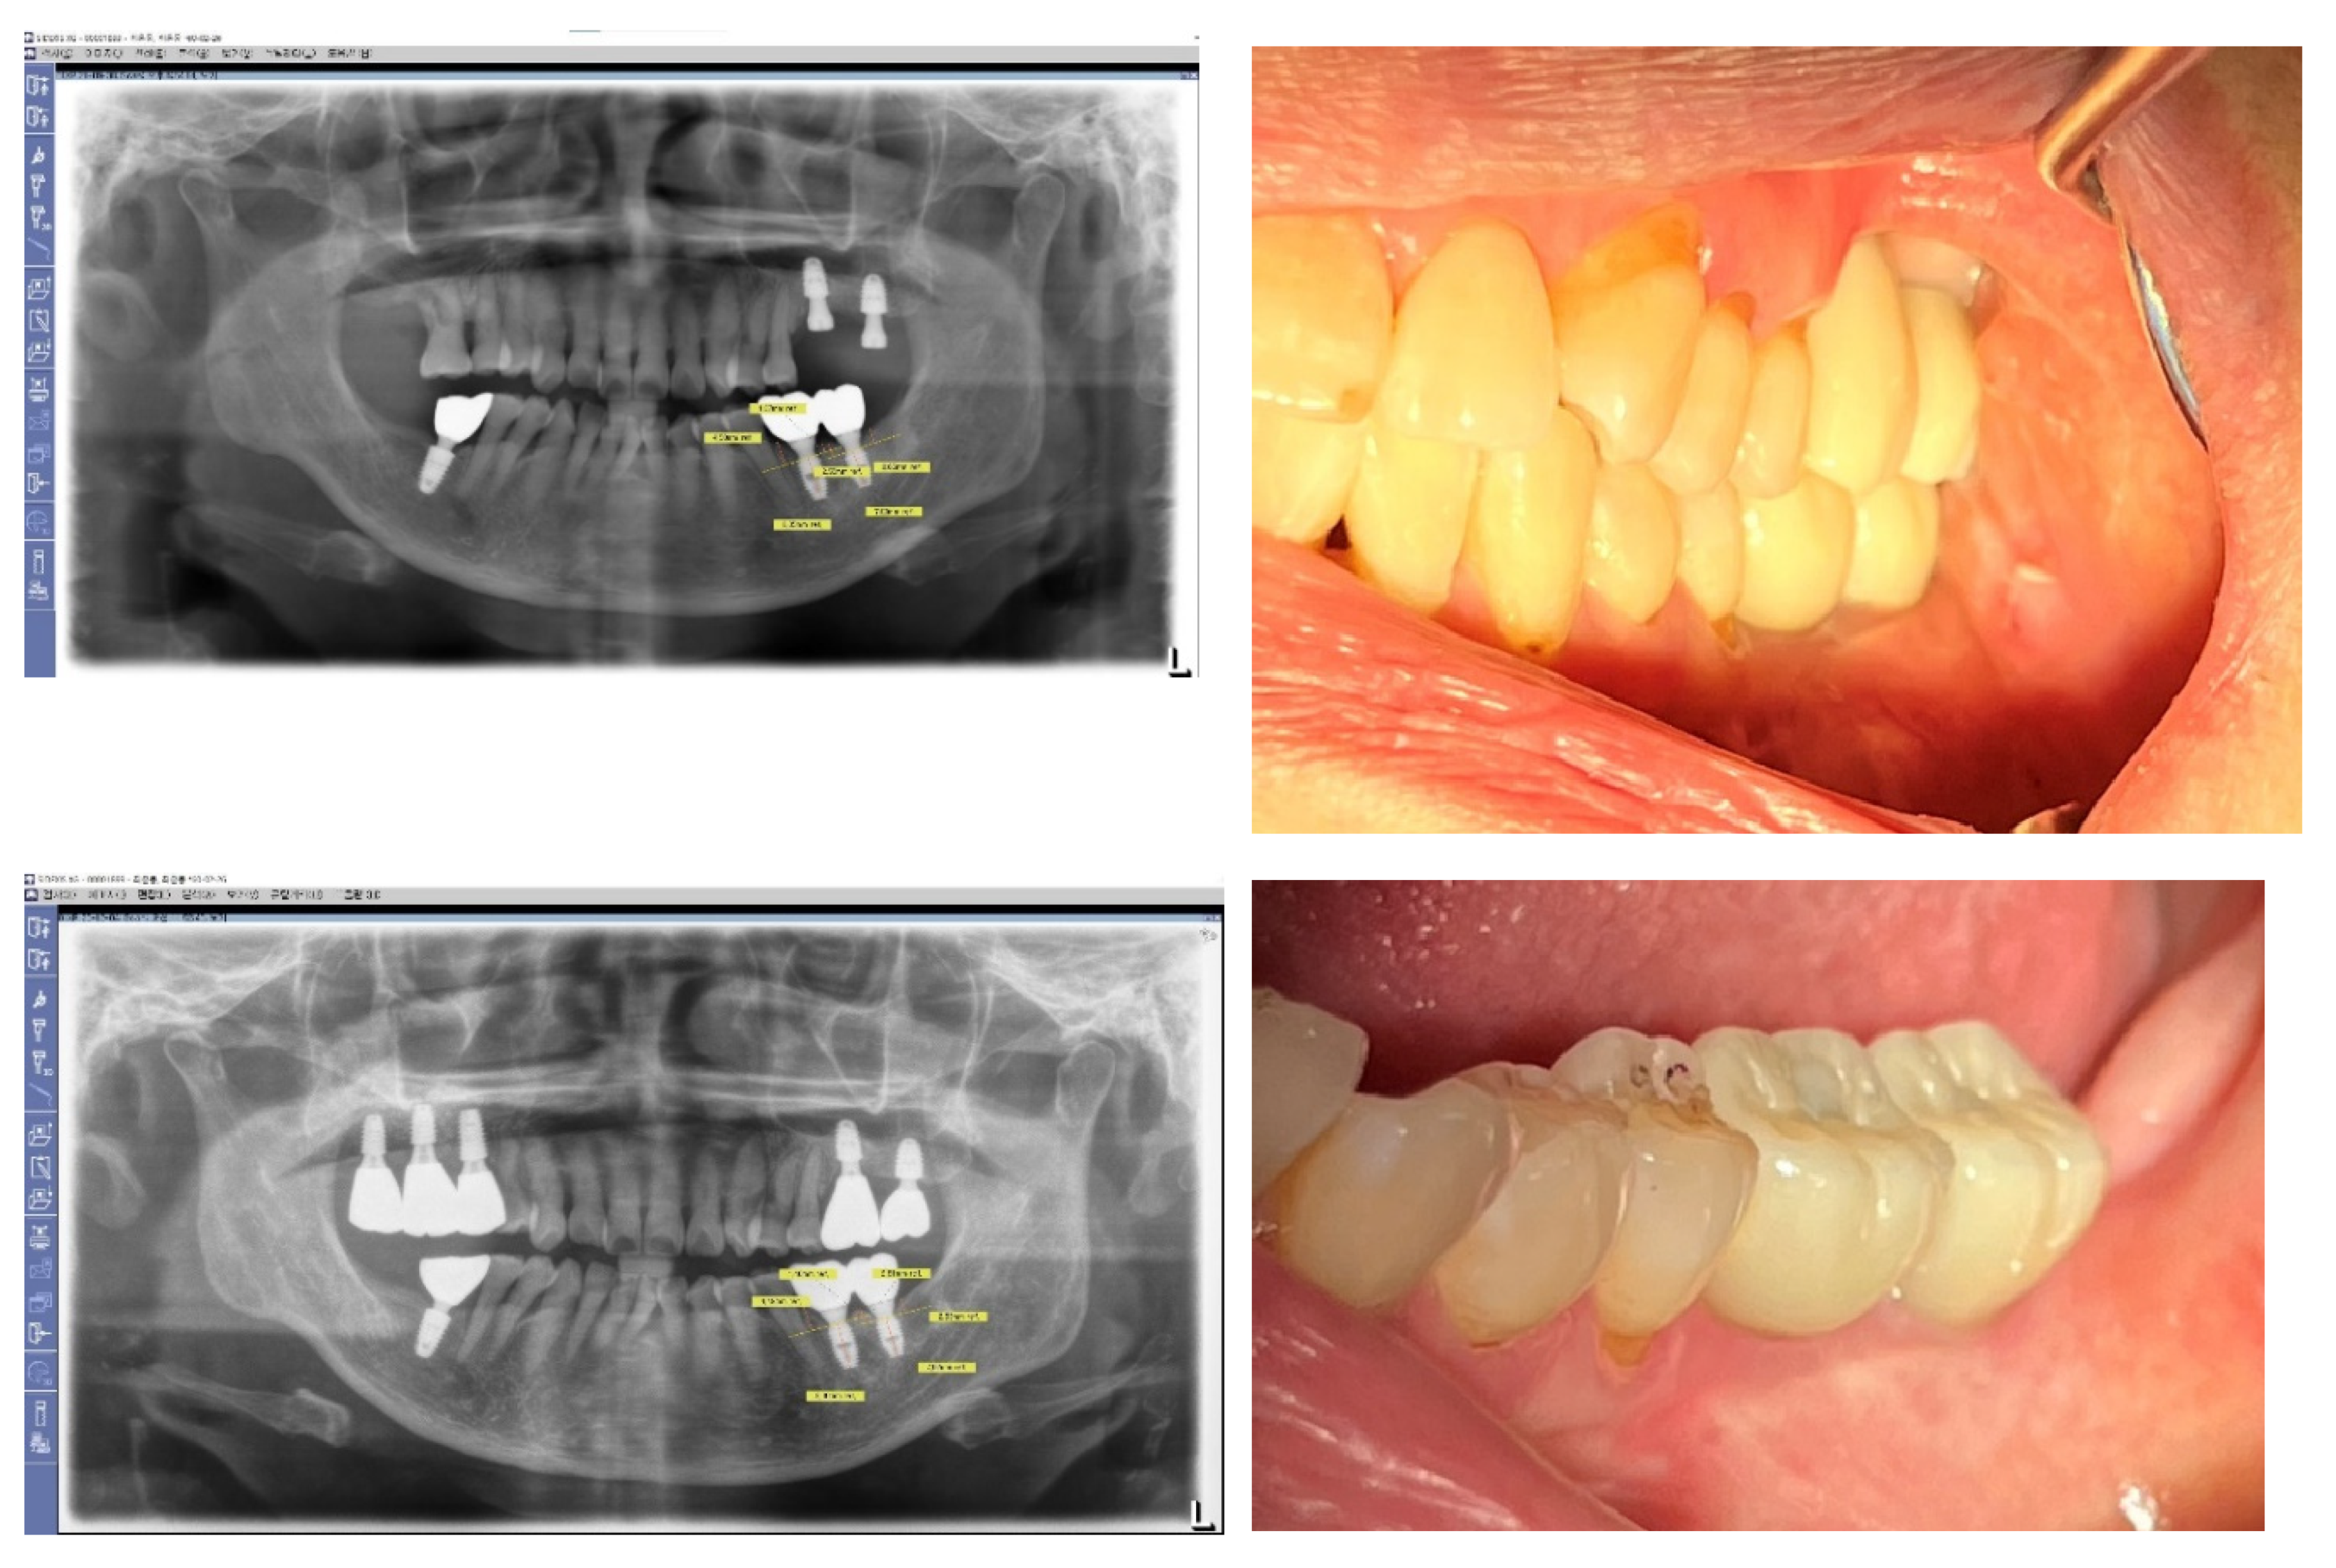

Figure 22. Natural-Looking Results Achieved by SPI Technique. This figure illustrates the effectiveness of the Subcrestally Placed Implants (SPI) technique in achieving results that closely mimic natural teeth. It demonstrates how the biologic width—comprising the transitional zone and subcrestal zone connective tissue—differs from that of natural teeth.

Figure 3 and Figure 4: Impact of Implant Placement Depth on Clinical Crown Shape

These figures demonstrate the effect of the depth of implant placement on the shape of the clinical crown. Figure 3 shows an equicrestal placement of a second molar implant, where insufficient vertical space necessitates a smaller diameter or an abrupt emergent profile for the clinical crown. In contrast, Figure 4 illustrates a subcrestal placement for a first molar implant, which provides sufficient vertical space allowing for the creation of a more natural-looking clinical crown with a gradual emerging profile.

Figure 3. Case Study of Epi-Crestal Placement of a Second Molar Implant. This figure illustrates a case where a second molar implant was placed epi-crestally, resulting in a smaller clinical crown size and an unnatural appearance due to an improper emergent profile compared to the adjacent natural molar. This outcome is attributed to the shallow depth of placement, which causes the transition part to be exposed supramucosally.

Figure 4. Comparative Case of Equicrestal vs. Subcrestal Implant Placement. This figure demonstrates the differences between equicrestal and subcrestal implant placements. For the implant in the position of the second molar, equicrestal placement results in a molar diameter reaching a short vertical distance, leading to an abrupt emergent profile with the transition part located supramucosally. In contrast, for the implant in the position of the first molar, subcrestal placement yields a more natural appearance, as it allows for a gradual emergence with the vertical distance matching the horizontal distance needed for diameter increase, and the transition part located submucosally.